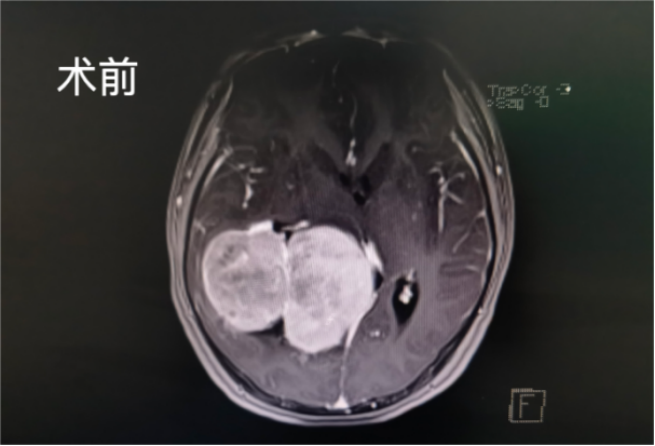

左圖白色為腫瘤,右圖顯示腫瘤全切

然而,好景不長,不到一年時間,小君近日頻繁出現頭痛,再次到醫(yī)院就診,原來罪魁禍首是顱內腫瘤“長大了”。從影像片子上看,這個巨大腦室腫瘤約鵝蛋大小,形似“葫蘆”。

術后,小君被轉入神經重癥監(jiān)護室治療,術后復查CT顯示腫瘤被全切。目前,小君已康復出院,無神經功能障礙。